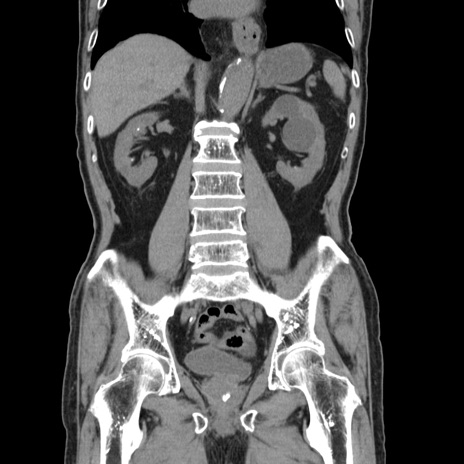

症例24(冠状断像)

【症例】80歳代男性

【主訴】左側腹部痛、嘔吐

【現病歴】本日早朝より左腹部に痛みあり。昼頃嘔吐認めたため、救急要請。

【既往歴】直腸癌(Mile手術)、胆摘

【身体所見】意識清明、BT 35.9℃、BP 221/93mmHg、SpO2 97%(RA) 、腹部:左ストーマ周囲に限局性の腹部膨隆あり。 膨隆部自発痛・圧痛あり・軟。

【データ】WBC 7700、CRP 0.09